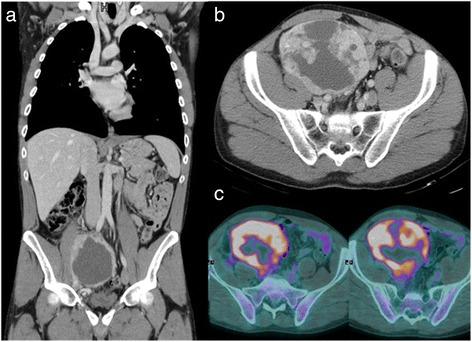

Dendritic cell tumors are extremely rare neoplasms and occur both in nodal and extranodal sites. We report a case of an intra-abdominal follicular dendritic cell sarcoma (FDCS). The aim of this study is to describe histological, immunohistochemical, and ultrastructural features of FDCS in order to better define an abdominal mass with unusual immunophenotype and atypical clinical and radiological presentation.

树突状细胞肿瘤极为罕见,可发生于淋巴结及结外部位。我们报告一例腹腔内滤泡树突状细胞肉瘤(FDCS)。本研究旨在描述FDCS的组织学、免疫组化及超微结构特征,以便更好地明确具有不寻常免疫表型以及非典型临床和影像学表现的腹部肿块。